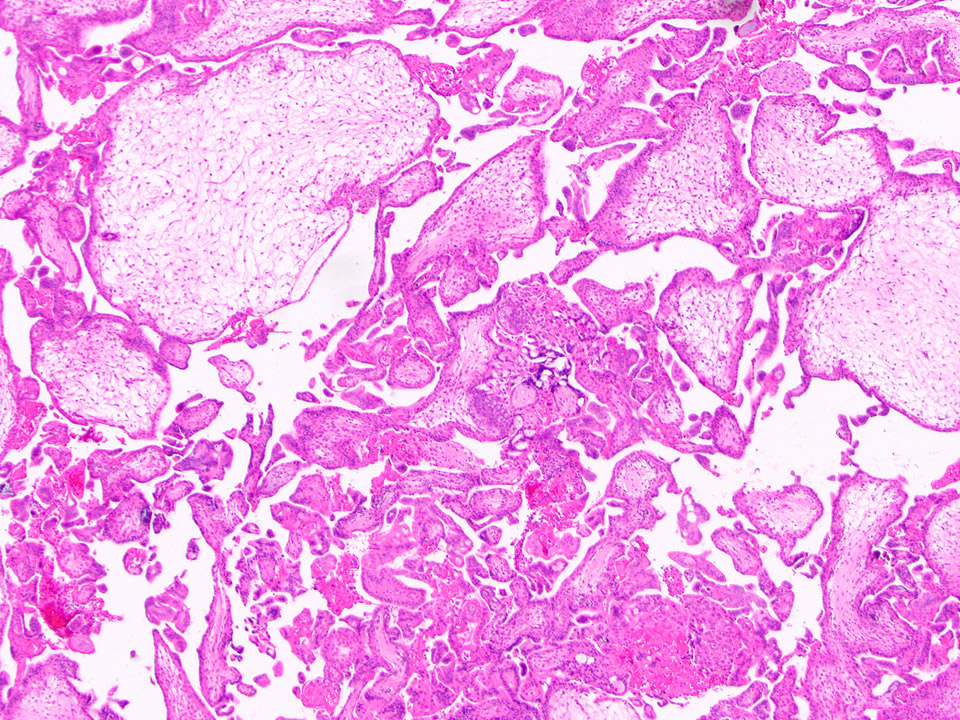

Microscopic (histologic) description

- Removed or passed products of conception may contain:

- Spectrum of villous changes in immature chorionic villi following embryonic death (Placenta 2005;26:114):

- Cellular debris within villous vessels - earliest change

- Villous edema with myxoid stromal degeneration - may be confused with molar gestation

- Collagenized avascular villi (villous sclerosis / fibrosis)

- Villous edema and sclerosis / fibrosis often coexist

- Spectrum of villous morphology in nonmolar abnormal karyotype (Hum Pathol 1995;26:201):

- Dysmorphic appearance (lacks sensitivity and specificity): highly irregular villous shapes / outlines, occasional trophoblastic inclusions

- Gestational / decidualized endometrium:

- Not uncommon to see inflammatory cells, especially lymphocytes but not plasma cells (plasma cells are pathologic)

- Variable amount of decidual necrosis with inflammatory debris

- Placental implantation site:

- Extravillous trophoblast (EVT) within decidualized endometrium, visible maternal vascular remodeling, fibrinoid material in decidua, EVT within vascular wall or within vessel lumens

- Confirms intrauterine pregnancy even in the absence of chorionic villi

Microscopic (histologic) images

Contributed by Chrystalle Katte Carreon, M.D. and Drucilla J. Roberts, M.D.